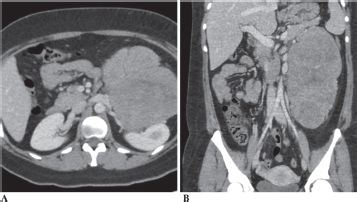

She underwent a computerised tomography (CT) scan, which revealed a large 21 × 15 cm mass, which appeared to be abutting the left kidney, left renal vessels, distal pancreas and spleen (Figure 1). She was admitted for further workup. Tumour markers including CEA, CA19-9, AFP and CA-125 were all within normal limits. Hormonal workup, including plasma free metanephrines, 24-hour cortisol, renin, aldosterone levels, was unremarkable. She underwent a core needle biopsy of the mass. Despite review by pathologists across multiple institutions, the results remained inconclusive. A preliminary diagnosis of a non-functioning paragangliomas (PGL) was made after an electron microscopic review. Patient was empirically started on Doxazosin, a selective alpha-blocker, 2 mg at bedtime for 4 weeks preoperatively for presumed PGL. The patient was subsequently taken to the operating room for exploratory laparotomy. After careful dissection, the mass was seen lying anterior to the left kidney. There was a clear demarcation between the structures; there was no evidence of invasion into the left kidney or its vasculature, and the left adrenal gland was uninvolved. The mass was carefully dissected, preserving the left kidney, ureter and renal vasculature. Postoperative period was uneventful, and she was discharged on postoperative day 4.

Figure 1. CT Abdomen (1A-Axial section and 1B-Coronal section) showing a 21 × 15 cm mass abutting the left kidney, left renal vessels, distal pancreas and spleen.